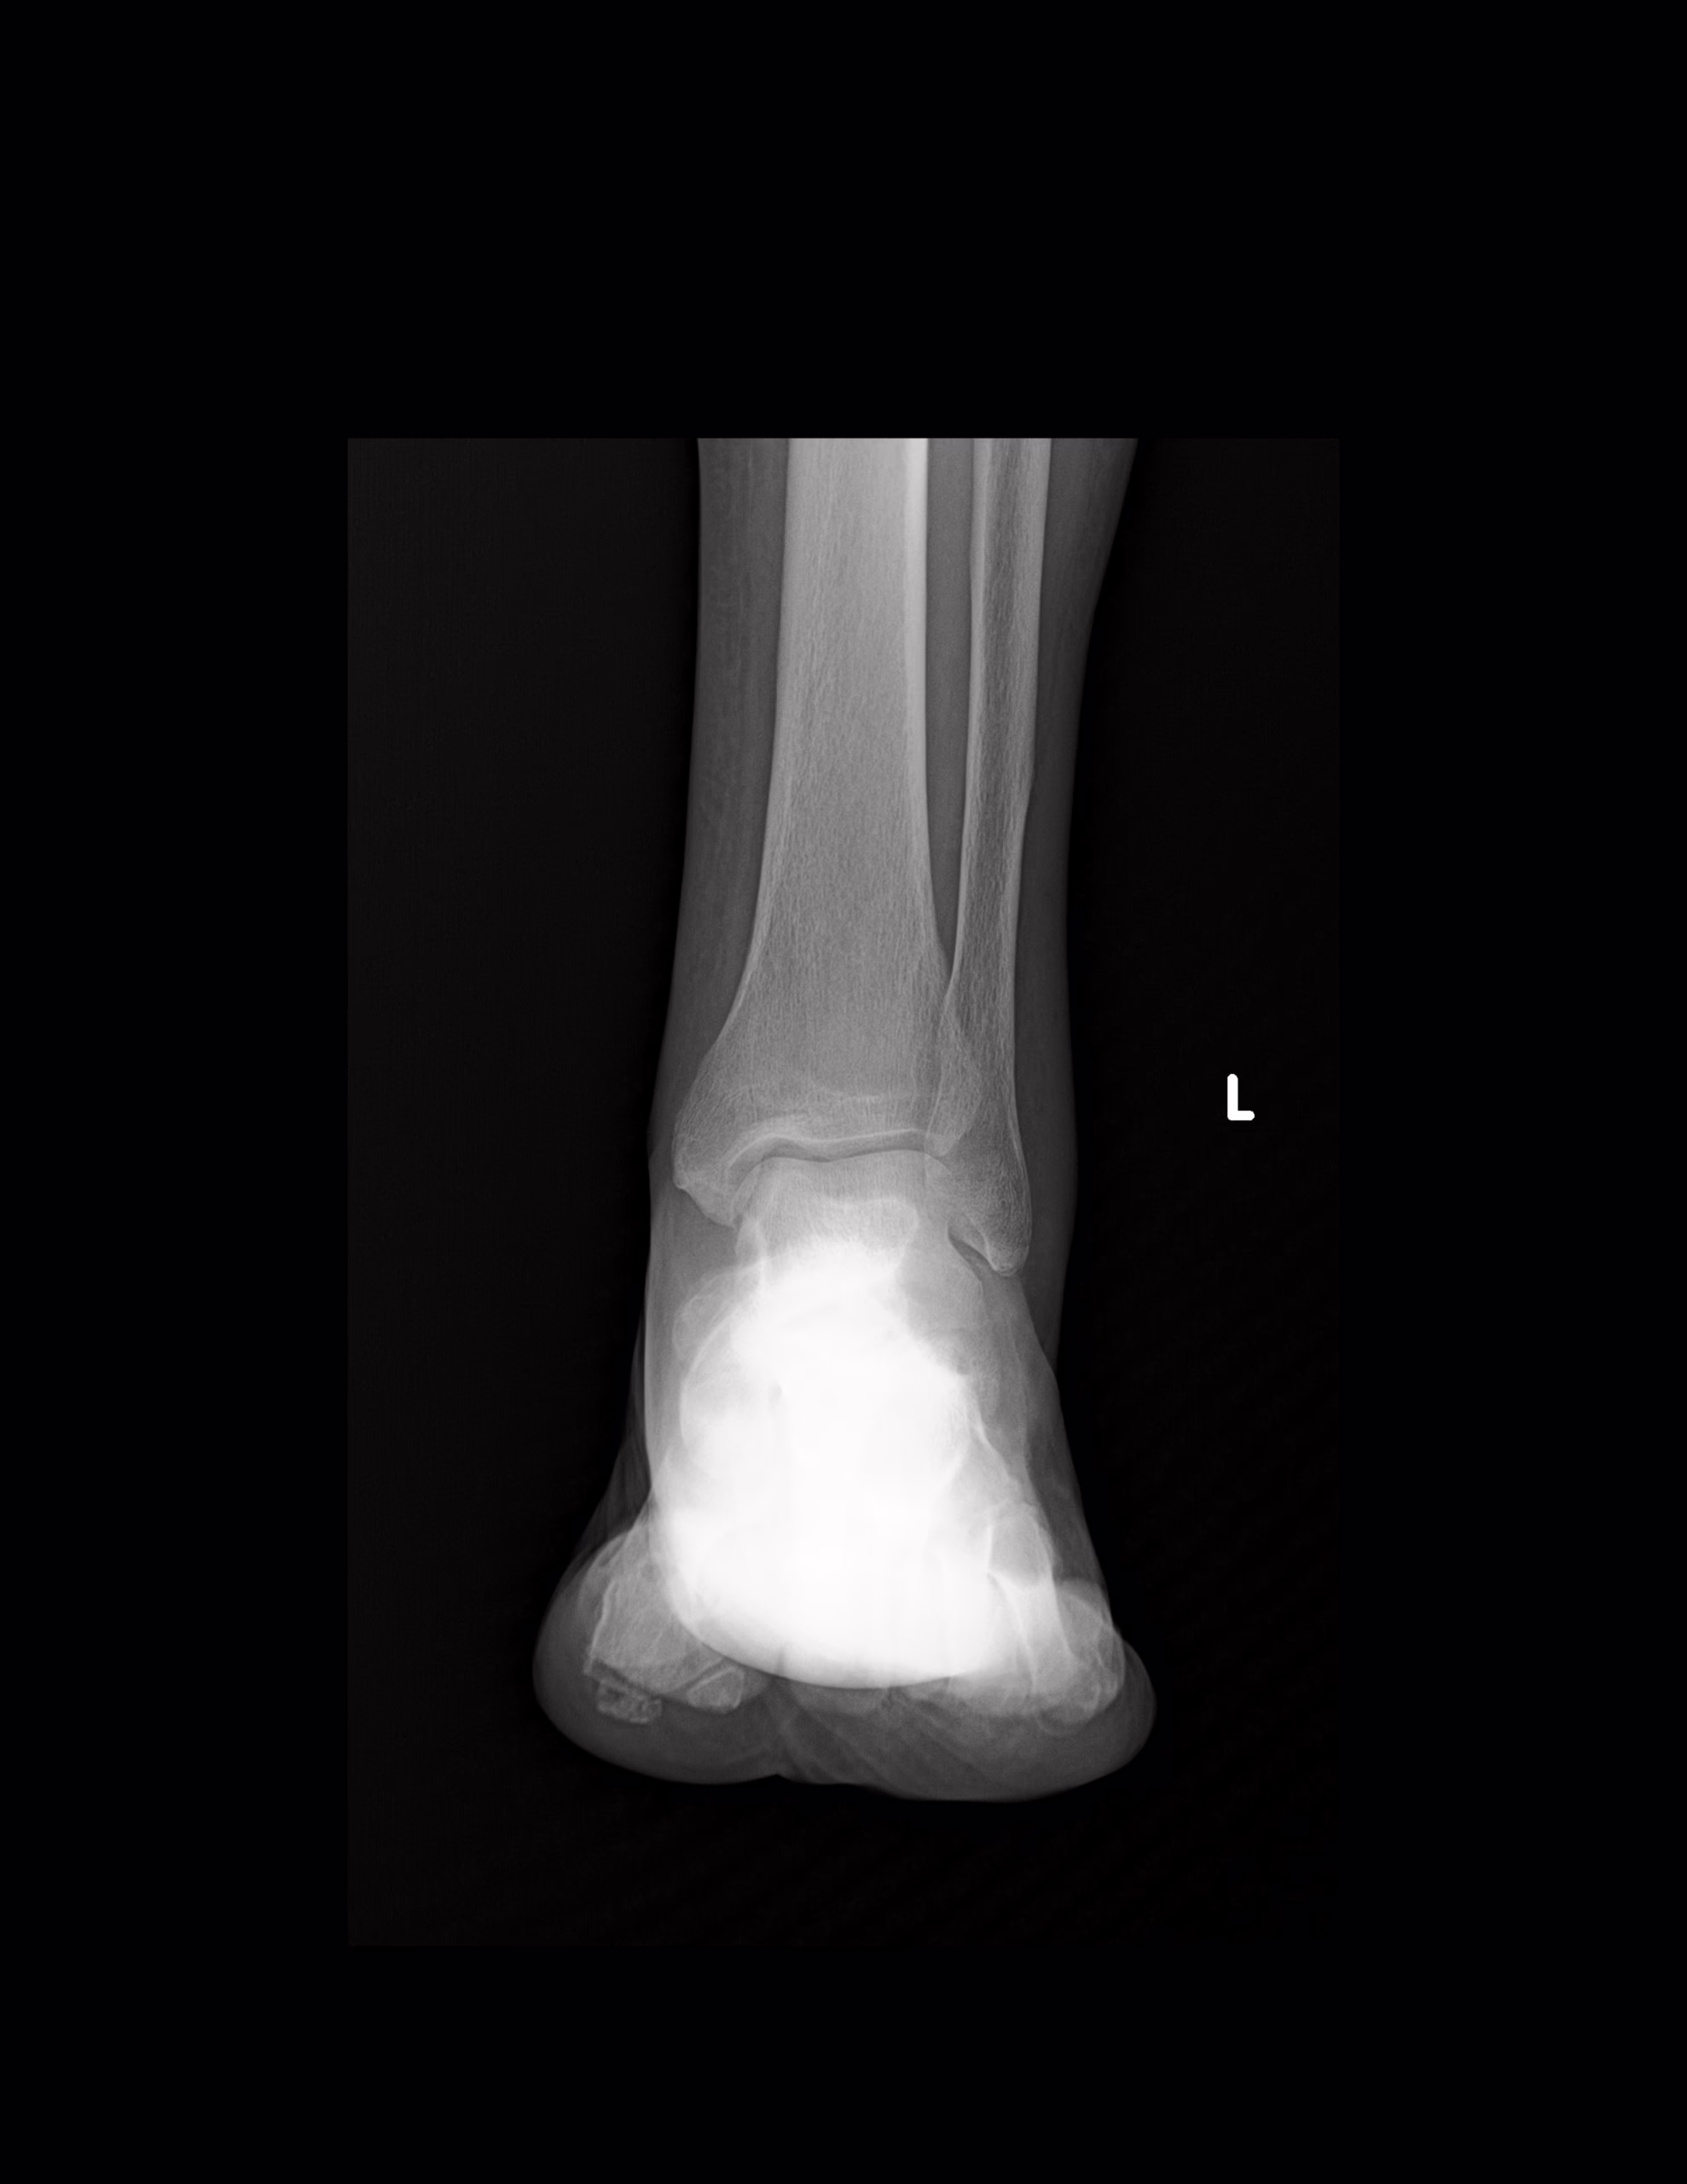

RADIOGRAFIA AP Y LATERAL DE TOBILLO

LAS PROYECCION RADIOLOGICA OBTENIDA NOS MUESTRA LOS SIGUIENTES HALLAZGOS

-Tejidos blandos, con aumento de la densidad y grosor a nivel posterior.

-De lo observado de tibia y peroné, sin evidencia de lesiones líticas, blásticas o perdida de la contigüidad.

-Existe fractura a nivel de proceso posterior de astrágalo con involucro de porción superior del calcáneo. Existe espícula osteofítica en porción inferior de tuberosidad del calcáneo. Resto de huesos del tarso y metatarsos, sin evidencia de lesiones líticas, blásticas o perdida de la contigüidad.

-Sombra tibioperonea mide 8.8 mm.

-Intervalo tibioperoneo de 5.98 mm.

-De lo observado de espacios articulares, sin evidencia de alteraciones.

OPINIÓN RADIOLÓGICA:

EN EL PRESENTE ESTUDIO RADIOGRÁFICO, EXISTE FRACTURA DEL PROCESO POSTERIOR DEL ASTRÁGALO E INVOLUCRO SUPERIOR DEL CALCÁNEO, CON EDEMA ASOCIADO.